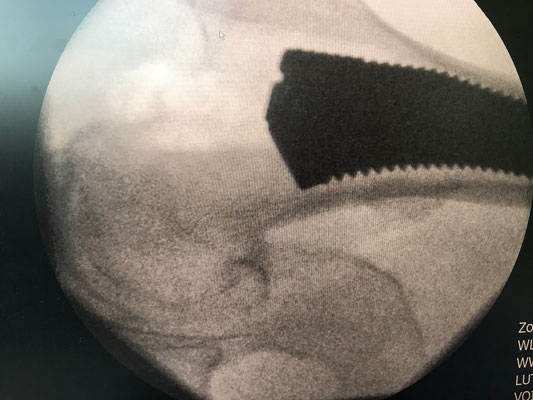

Die SUPERPATH Hüfte : In günstigen Fällen wird das künstliche Gelenk in einem minimalen Verfahren von oben hinten eingebaut. Die Vorteile: keine Muskelabtrennung, Erhaltung der Hüftkapsel, die Hüfte muss nicht während der Operation ausgekugelt werden. Dadurch kann frühzeitig auf Krücken verzichtet werden, der Blutverlust ist sehr gering, Thrombose und Gefahr der Ausrenkung sehr gering im Vergleich zu anderen Methoden.